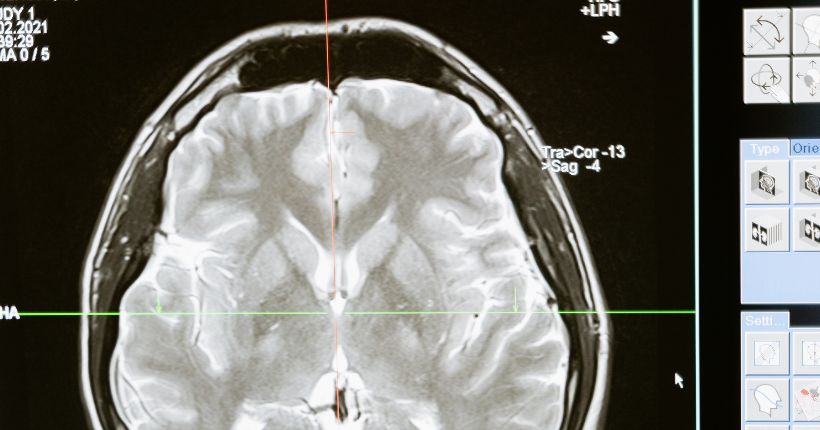

Desde 1996 se celebra cada marzo la Semana Mundial del Cerebro, una fecha creada por las organizaciones Dana Alliance for Brain Initiatives (DANAI) y la European Dana Alliance for The Brain (EDAB) que propone concienciar a la población sobre la importancia de una óptima salud. Cerca de 160 organizaciones y asociaciones profesionales, universidades, hospitales y agencias gubernamentales participan en esta campaña, que engloba a 7.300 socios en 120 países.

La concientización sobre las enfermedades relacionadas con el cerebro y su prevención son una importante parte de esta campaña, así como el apoyo a la investigación en neurociencias.

Todo ello forma parte de una gran campaña de prevención de las enfermedades neurológicas y de sensibilización sobre la importancia del cuidado de nuestro cerebro.